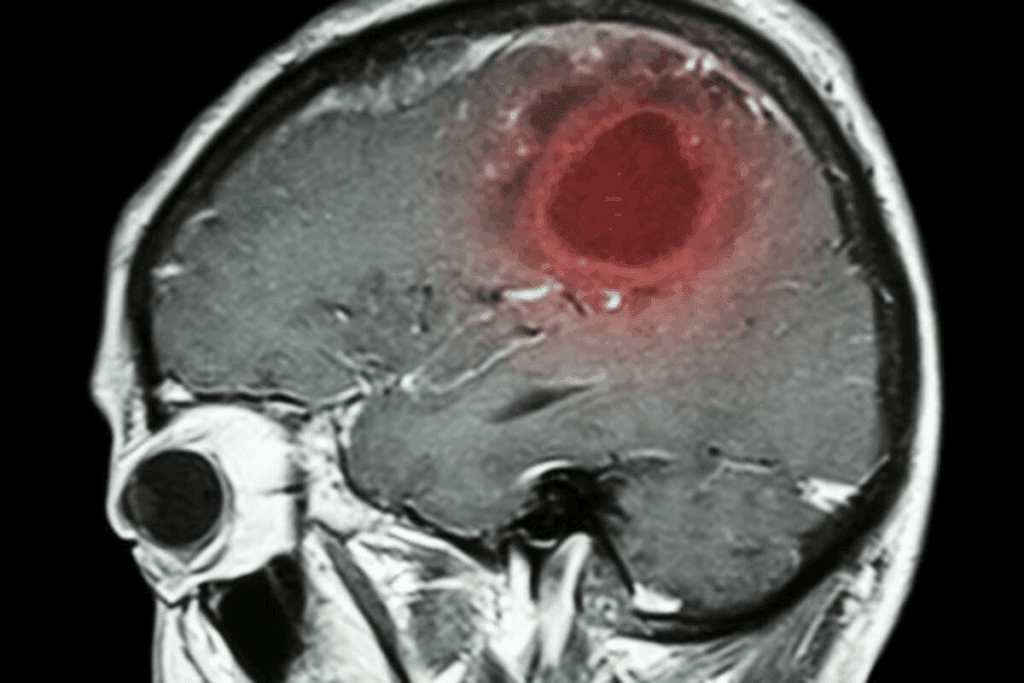

A brain tumor is a mass of abnormal cells in the brain. It can be primary or secondary. Primary tumors start in the brain, while secondary ones spread from other parts. Knowing this is key.

A brain tumor is when cells in the brain grow out of control. They can be benign or malignant. Benign tumors are not cancerous and don’t spread. Malignant tumors are cancerous and can grow into other brain tissue.

Imaging techniques are very important for finding brain tumors. Magnetic Resonance Imaging (MRI) and Computed Tomography (CT) scans are the main tools. MRI shows soft brain tissues well, while CT scans spot bone and calcification issues.

These scans help doctors see the tumor’s size, location, and how it might harm nearby brain areas.